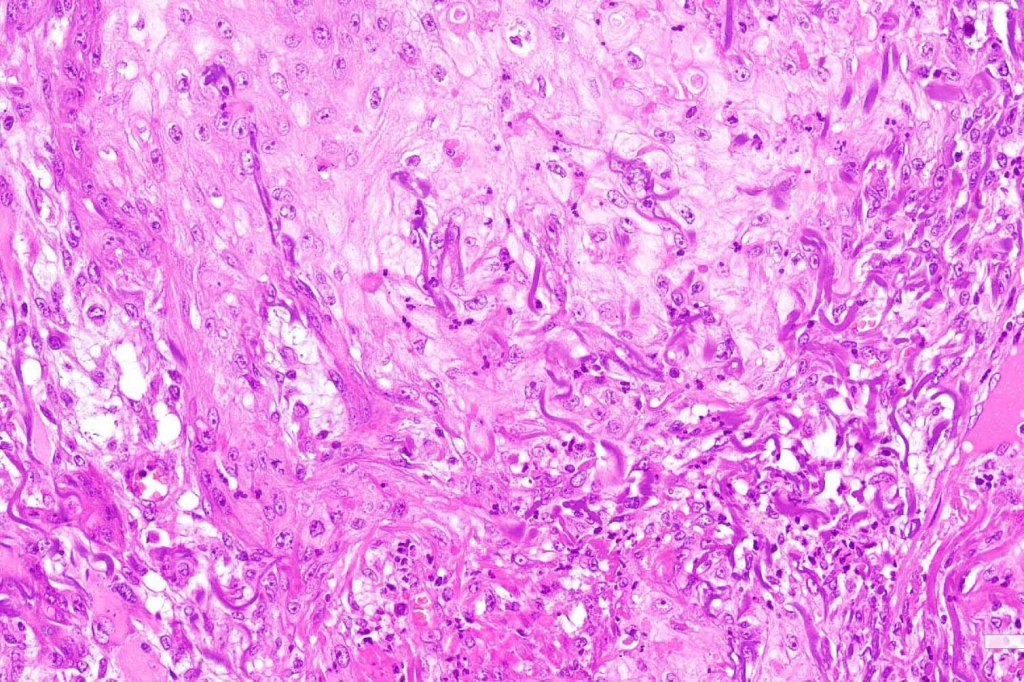

Below is a fascinating case shared on McKee Derm by Dr. James Simpson. There is an obvious keratoacanthoma but at the edge of the lesion there is marked atypia with nuclear enlargement and pleomorphism. This is also evident in the adjacent epidermis and in the deeper nests.